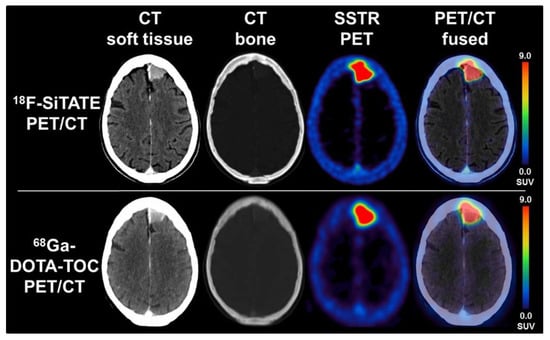

- Unterrainer, M.; Lindner, S.; Beyer, L.; Gildehaus, F.J.; Todica, A.; Mittlmeier, L.M.; Jurkschat, K.; Wängler, C.; Wängler, B.; Schirrmacher, R.; et al. PET Imaging of Meningioma Using the Novel SSTR-Targeting Peptide 18F-SiTATE. Clin. Nucl. Med. 2021, 46, 667–668. [Google Scholar] [CrossRef]

- Niedermoser, S.; Chin, J.; Carmen, W.; Kostikov, A.; Bernard-gauthier, V.; Vogler, N.; Soucy, J.; Mcewan, A.J.; Schirrmacher, R. In Vivo Evaluation of 18F-SiFAlin-Modified TATE: A Potential Challenge for 68Ga-DOTATATE, the Clinical Gold Standard for Somatostatin Receptor Imaging with PET. J. Nuc. Med. 2015, 56, 1100–1105. [Google Scholar] [CrossRef]

- Ilhan, H.; Lindner, S.; Todica, A.; Cyran, C.C.; Tiling, R.; Auernhammer, C.J.; Spitzweg, C.; Boeck, S.; Unterrainer, M.; Gildehaus, F.J.; et al. Biodistribution and first clinical results of 18 F-SiFAlin-TATE PET: A novel 18 F-labeled somatostatin analog for imaging of neuroendocrine tumors. Eur. J. Nucl. Med. Mol. Imaging 2020, 47, 870–880. [Google Scholar] [CrossRef]